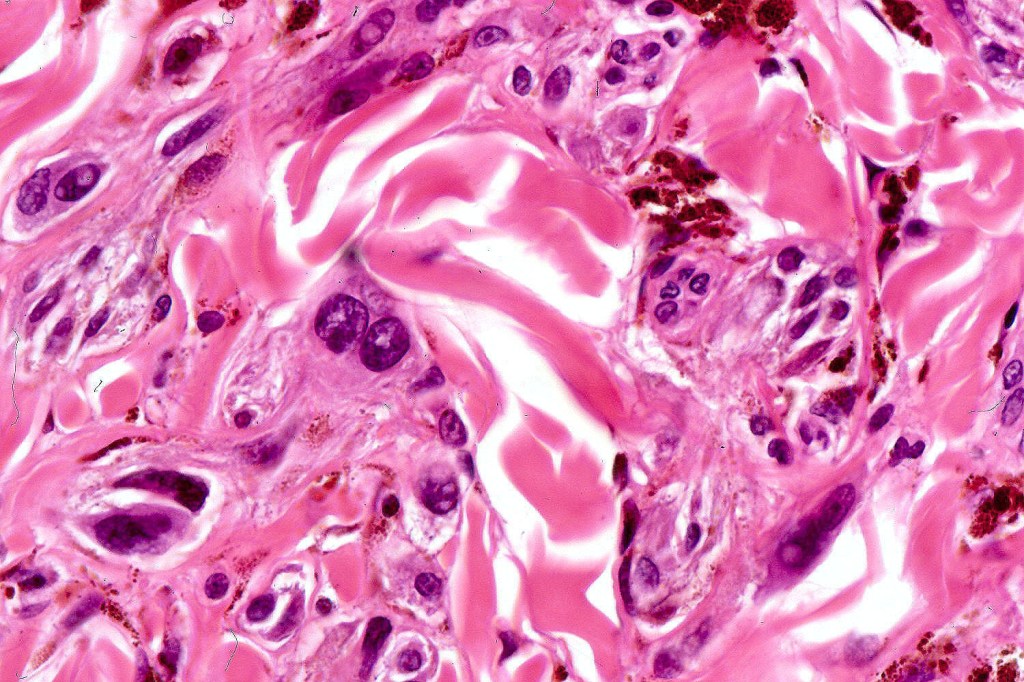

Cellular blue nevus

Histological features

•Most characteristic is the dumbbell silhouette although a plague morphology may also be encountered

•Combined nevus variant

•Admixture of spindle cells, pigmented bipolar or dendritic cells & melanophages

•Cytoplasm is pale and nuclei are small with inconspicuous nucleoli

•An alveolar pattern is characteristic particularly with clear cell nodules

•Mitoses are typically very sparse or absent

•No atypical mitoses

•No Necrosis or lymphovascular invasion

•Multinucleate giant cells sometimes present

•Stromal fibrosis, myxoid change, vascular hyalinization with cyst formation are often seen

•Some tumors are composed spindle cells in a fascicular or neuronevoid pattern

•Perineural involvement may be seen

•Balloon cell change

•Desmoplastic variant

•Hypopigmented variant